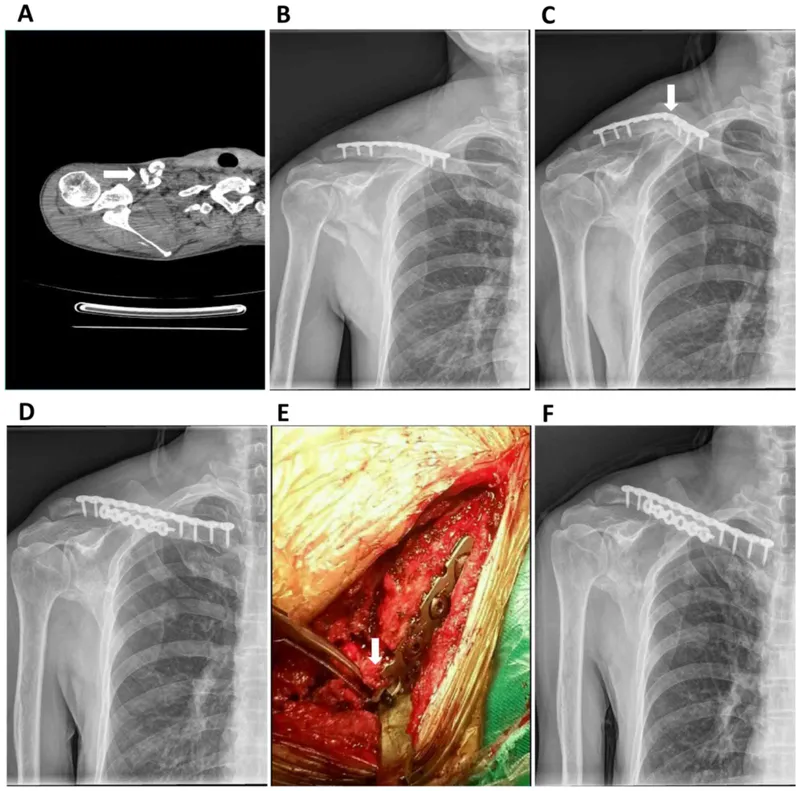

- LCP (Locking Compression Plate): Locking/non-locking screws; angular stability. Internal fixator.

- Specialty: Anatomical (PHILOS, condylar buttress).

⭐ LCPs: internal fixators, angular stability independent of plate-bone friction. Ideal for osteoporotic bone & comminuted periarticular #.